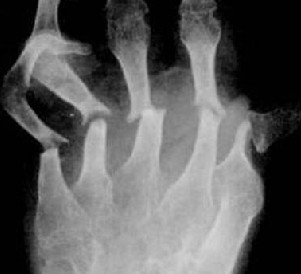

类风湿有叫做类风湿性关节炎,是一种慢性的自身免疫疾病,对于这 ...

类风湿关节炎的病因至今并不十分明了,目前大多认为其是人体自身 ...